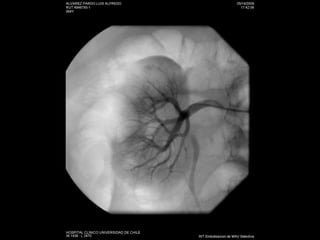

Angiografía

Embolización de lesionespostraumáticas vasculares renales.